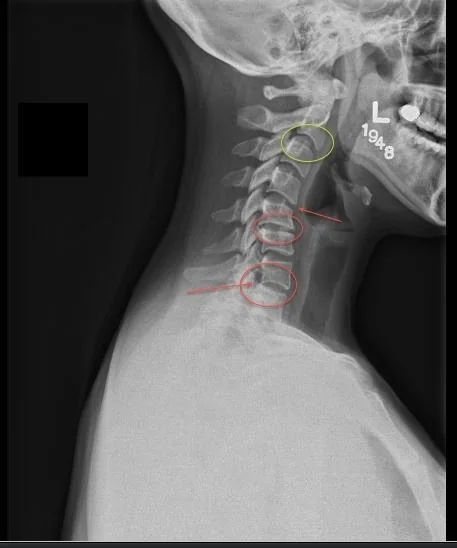

Le rôle des radiographies : voir ce qui ne fait pas nécessairement mal

Pour plusieurs, les radiographies créent un déclic.

Elles donnent enfin un sens à ce qui semblait incohérent :

Pourquoi je souffre maintenant? Pourquoi maintenant et pas avant? Pourquoi ça a “lâché” d’un coup?

Les radiographies n’expliquent pas toujours le symptôme exact du jour, mais elles montrent le terrain dans lequel vos douleurs apparaissent :

• Perte d’espace discal

• Arthrose

• Remodelage osseux

• Altération des courbures

• Calcifications

• Dégénérescences d’usure

Ces changements ne sont pas apparus en une semaine, ni en un mois.

Ils reflètent un processus installé depuis longtemps — tout comme un frigo qui fonctionne “correctement”, mais dont les composantes internes fatiguent depuis des années.